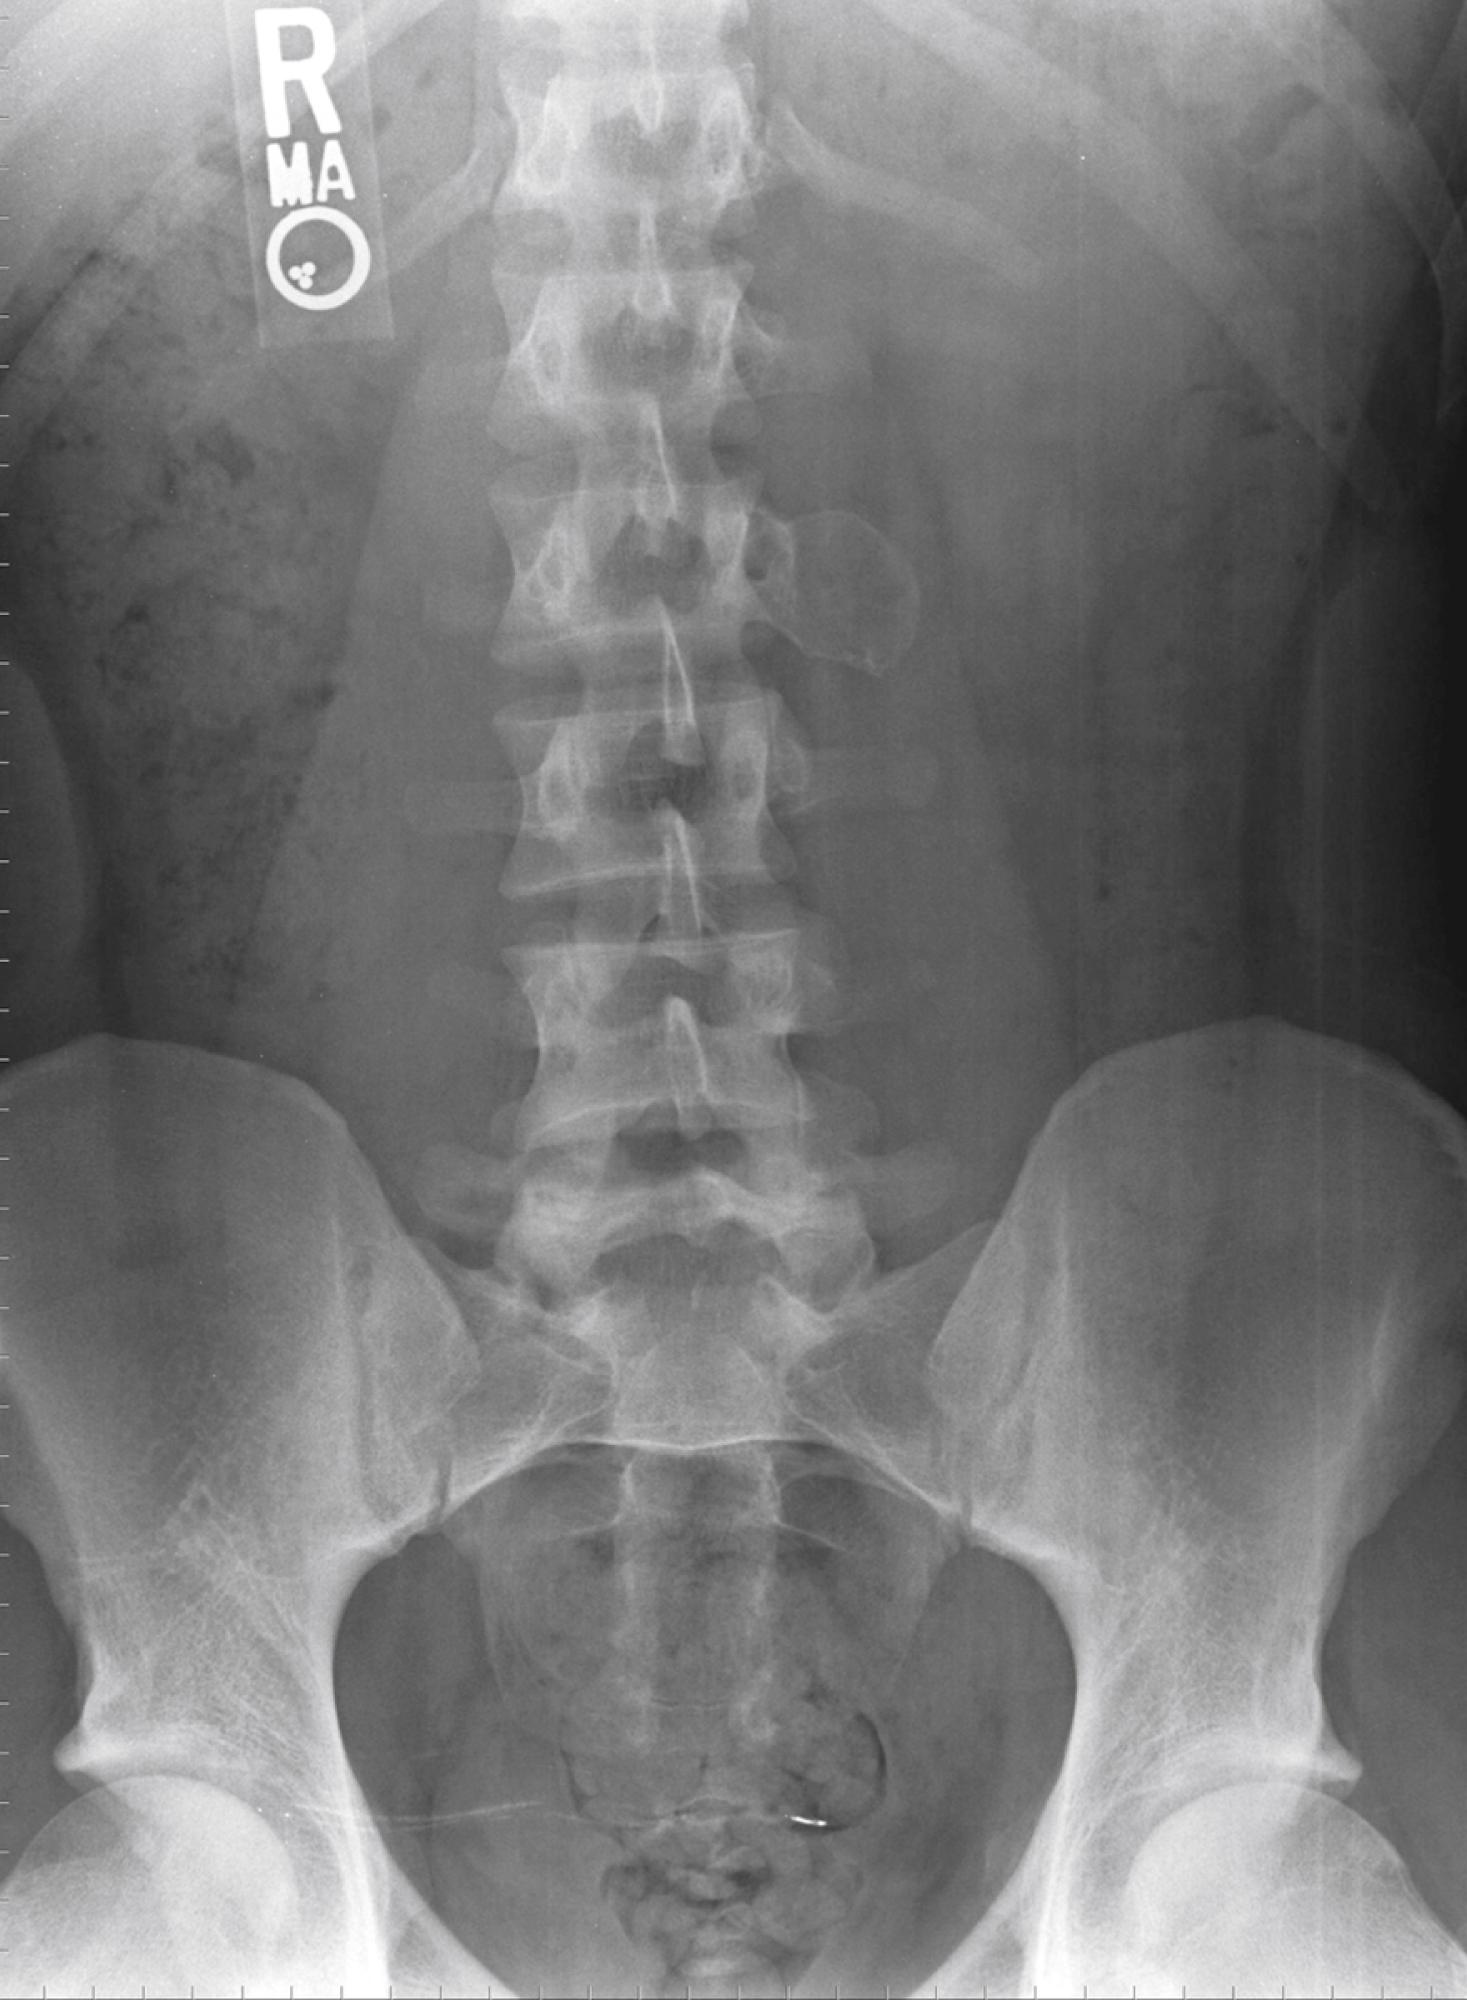

En bloc wide resection may be required in some stage 3 tumors, cases of local recurrence, and tumors recalcitrant to other methods of intervention. Around the knee, a hemicondylar osteoarticular allograft reconstruction or a rotating hinge endoprosthesis may be necessary ( Fig. 26.3 ). For aggressive lesions of the distal radius, primary resection and reconstruction with a proximal fibular autograft (either as an arthroplasty or as an arthrodesis) may be indicated ( Fig. 26.4 ). For lesions in expendable bones (e.g., the distal ulna, clavicle, or proximal fibula), primary resection without reconstruction may be indicated. For inoperable lesions in the spine or pelvis, irradiation or embolization (or both) may be used ( Fig. 26.5 ); however, caution is advised because of the risk of sarcomatous change in patients treated with irradiation. In patients with pulmonary metastases, resection should be attempted. Chemotherapy has limited success, and irradiation should be reserved for symptomatic inoperable lesions.

FIGURE 26.5, Giant cell tumor in 23-year-old woman.